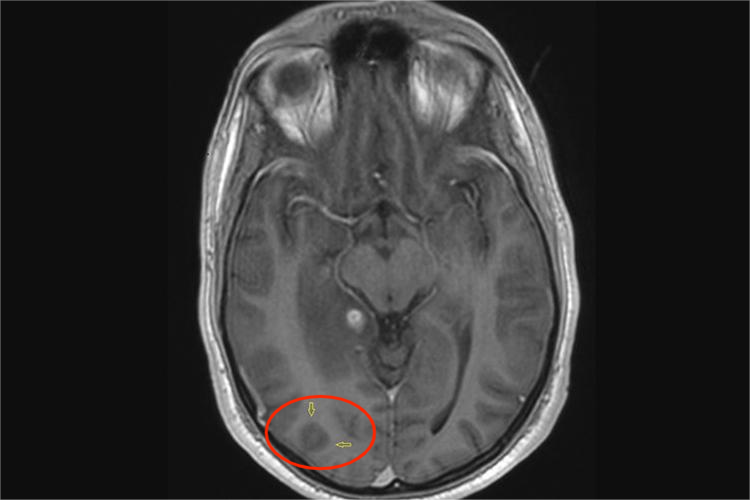

MRI表现

MRI影像学表现为结核球呈圆形、类圆形的结节或肿块,以单发多见,边缘光滑,少数边缘有分叶和毛刺。T1WI上病灶呈较低信号,T2WI上中心呈低信号,包膜呈高信号,伴有明显钙化者T1WI和T2WI均呈低信号,增强后周边包膜强化,常见斑点状或结节状卫星灶。